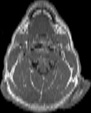

Visible Human male: Sectio transversalis 1229

CT

NMR

Pd T1 T2